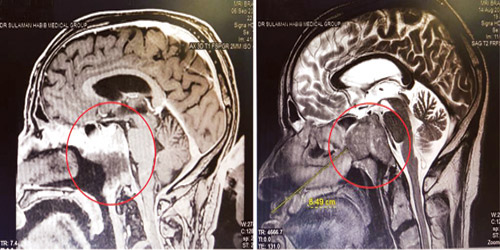

إنهاء معاناة سبعيني باستئصال ورم في قاع المخ في مستشفى د سليمان الحبيب بالقصيم